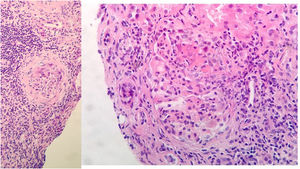

Evolución y pruebas complementariasA su ingreso, inicia tratamiento con levofloxacino, anticoagulación profiláctica con HBPM y soporte respiratorio. Evoluciona a mayor insuficiencia renal y respiratoria. Se realiza biopsia renal a los 10 días de ingreso, con juicio clínico de glomerulonefritis proliferativa extracapilar de tipo mixto pauciinmune asociada a ANCA con cambios crónicos moderados (imagen 2).

Biopsia renal: 11 glomérulos, 3 globalmente esclerosados. Cinco con cambios congestivos menores y 3 con proliferación extracapilar y formación de semilunas celulares Compartimento túbulointersticial con inflamación crónica y aguda, atrofia tubular del 30%, tiroidización tubular y fibrosis del intersticio del 30%. No cambios en vasos de mediano calibre, ni engrosamiento de la media arterial. No depósitos congófilos. Inmunofluorescencia directa con leve depósito mesangial granular de C3+, sin depósitos de IgG, IgM, IgA ni restricción de cadenas ligeras.